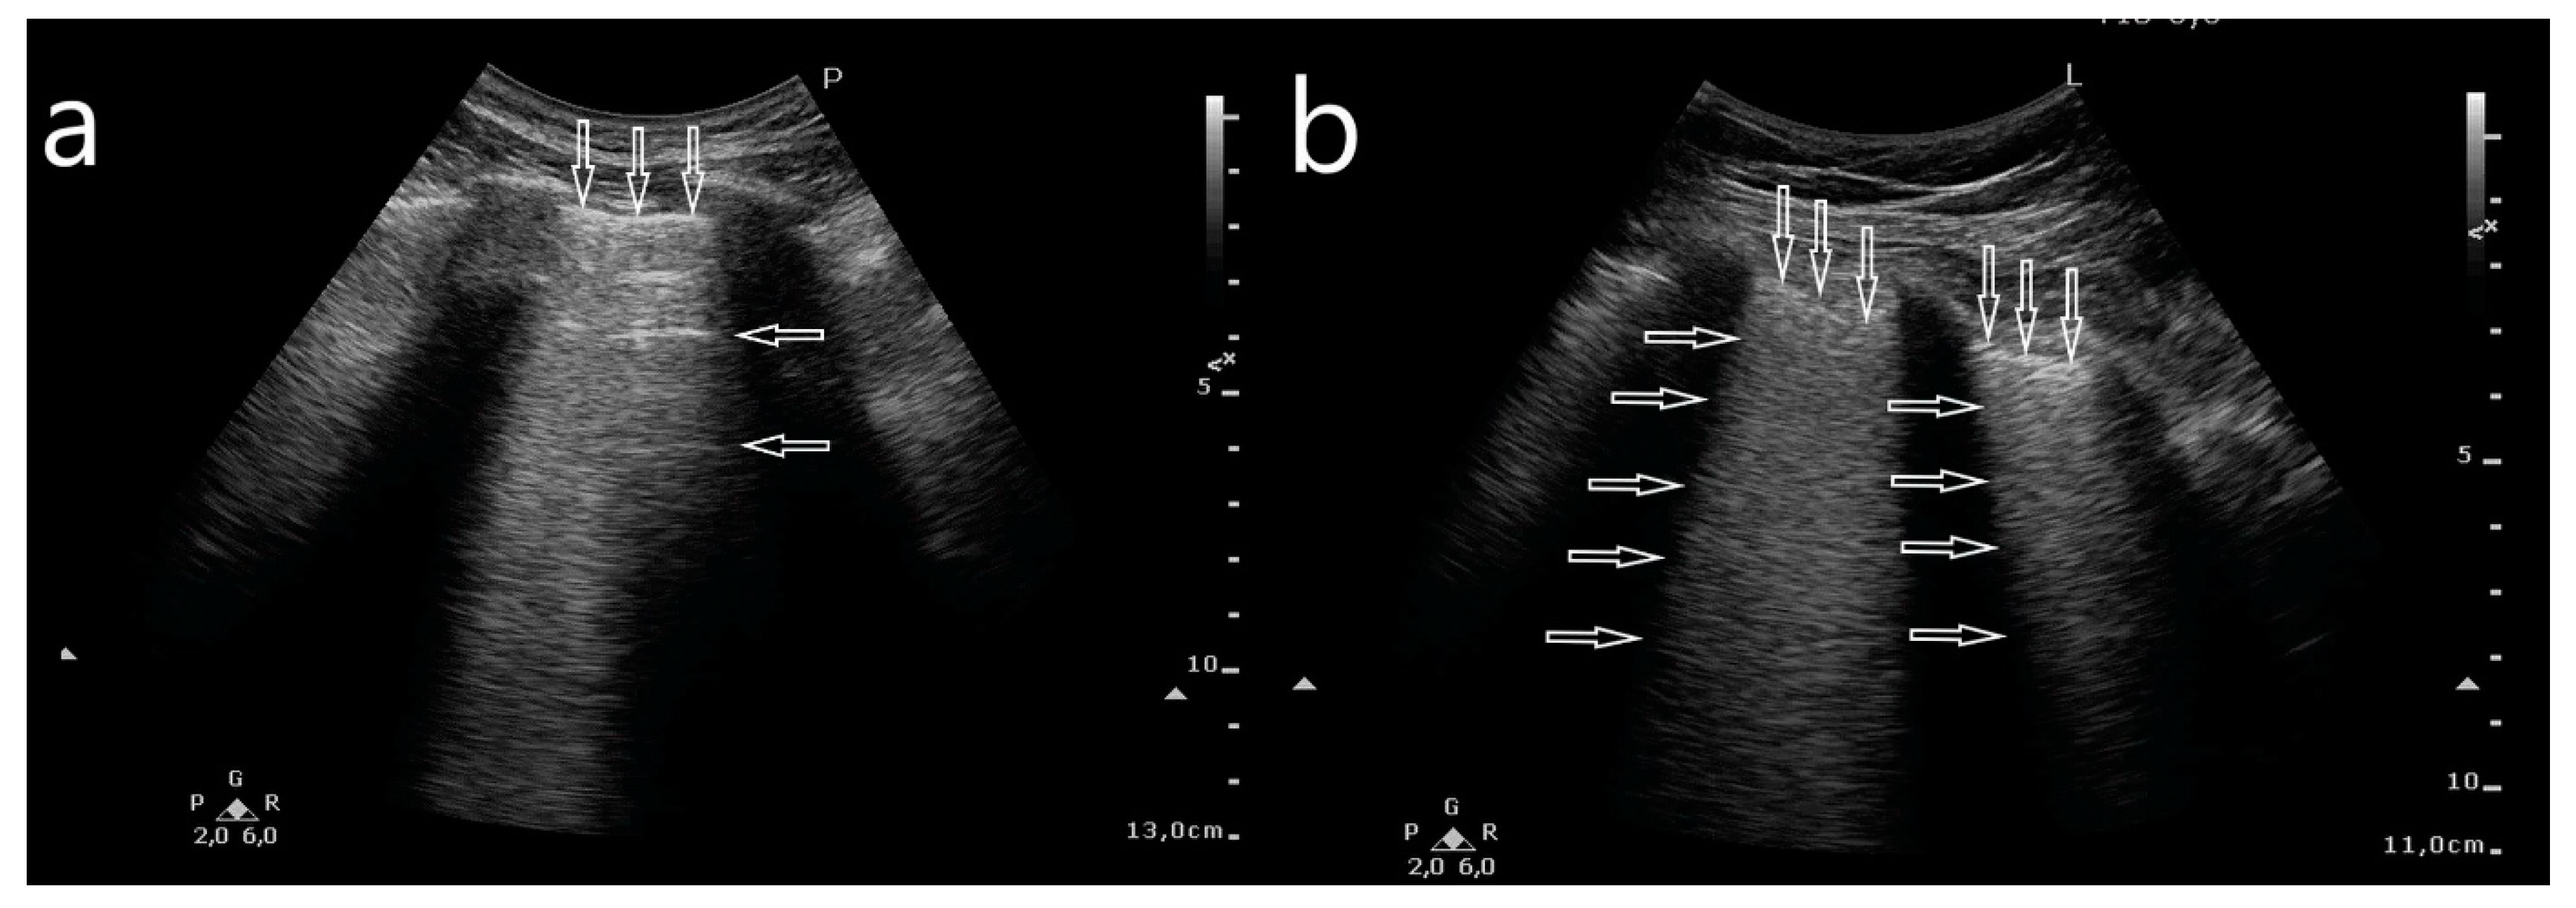

- Abnormalities within the pleural line (thickened, irregular, fragmented);

- Artifacts: multifocally located single B-line artifacts, multifocal multiple (confluent) B-line artifacts, bilateral and symmetrical B-lines, white lung, spared areas;

- Consolidations: small subpleural consolidations (up to 5 mm) accompanied with C-line artifacts, large consolidations involving segments and/or lobes, pleural effusion.

- Bilateral and symmetrical B-lines;

- White lung;

- Spared areas;